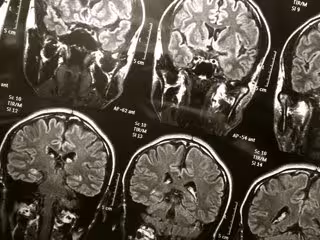

Vinculan las lesiones cerebrales traumáticas al riesgo de demencia

Cerebro

FLICKR/WYINOUE